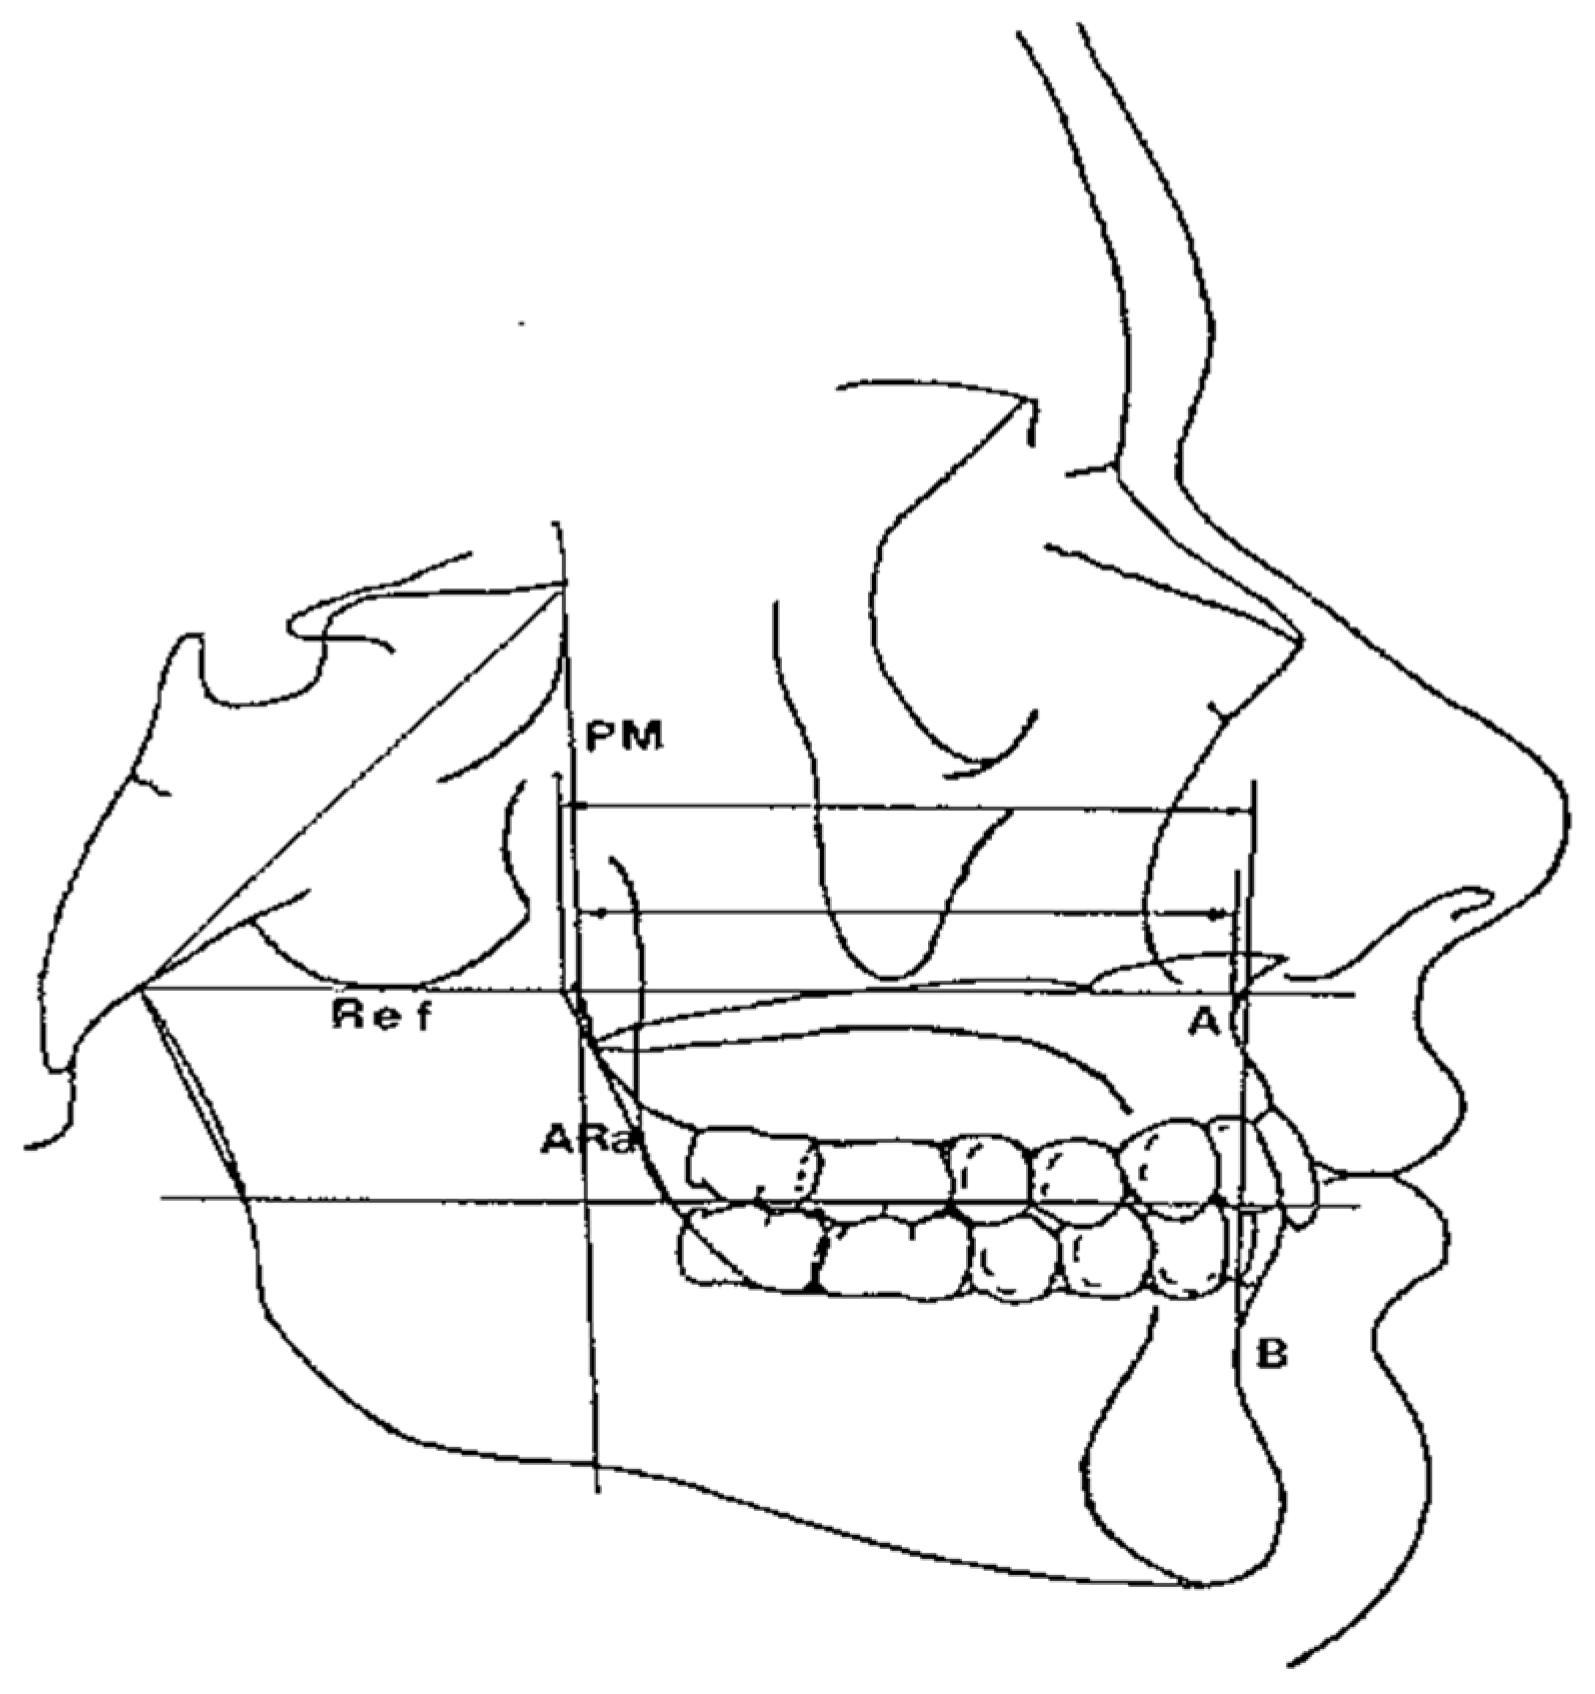

- Maxillary and Mandibular skeletal arches (Figure 1): this parameter compares the lengths of the maxillary and mandibular skeletal arches. The maxillary skeletal arch was measured by the distance between A point and PM, in parallel with Ref. The mandibular skeletal arch was measured by the distance between the orthogonal projection of B point on Ref and ARa, at its intersection point with Ref.

- Maxillary and Mandibular dento-alveolar arches (Figure 2): this parameter compares the lengths of maxillary and mandibular dento-alveolar arches. The maxillary dental arch was measured by the distance between PM and SPr, in parallel with Ref. The mandibular dental arch was measured by the distance between the orthogonal projection of IPr on Ref and Ara, at its intersection point with Ref.

- Middle Cranial Floor (MCF) and Mandibular ramus (Figure 3): this parameter compares the horizontal dimension of the middle cranial floor (Ar to neutral PM) and the width of the ramus (Ar to ARa). These parameters were measured along the Ref.